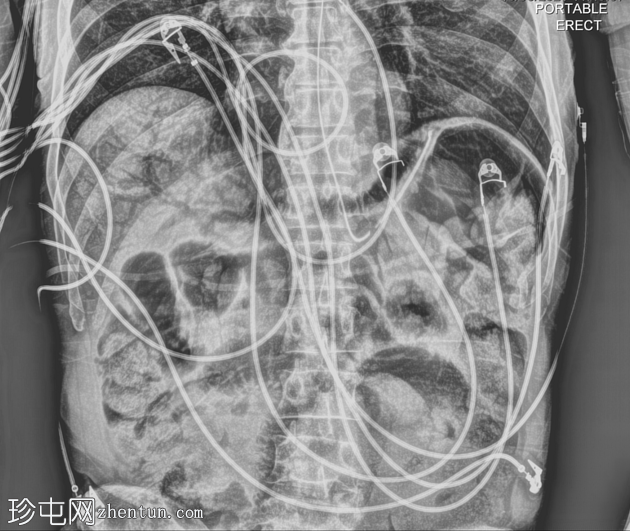

X线片

正位片

门静脉积气及肠壁积气。